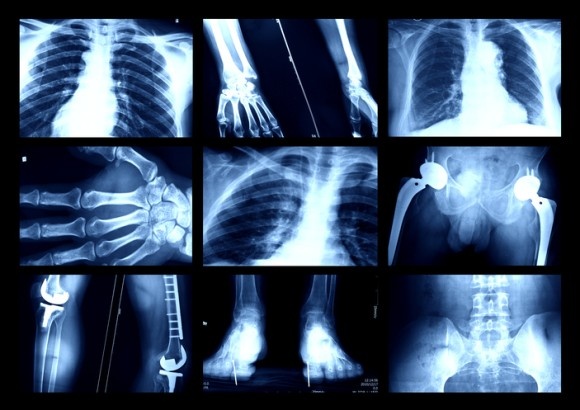

78歳のドメーニカはこれまで何度も骨折しているが、レントゲン撮影の結果、それに気が付くことなく自然に硬化していることがわかった。また火傷も平気なので皮膚には火傷の跡が数多く残されている。

ドメーニカの娘、レティツィア(52)はスキーで肩を骨折たが、その後もスキーを続け、運転して家に帰ってきたという。翌日になるまで自分が骨折したことに気づかなかったという。テニスをして、肘の骨を折ったときも同様だった。

レティツィアの息子、ルドヴィコ(24)はサッカーをやっているのだが足首にいくつも骨折の跡がみられた。次男のベルナルド(21)は自転車から転倒しやはり骨折していたのだが気が付かず、肘に骨折の跡があったという。